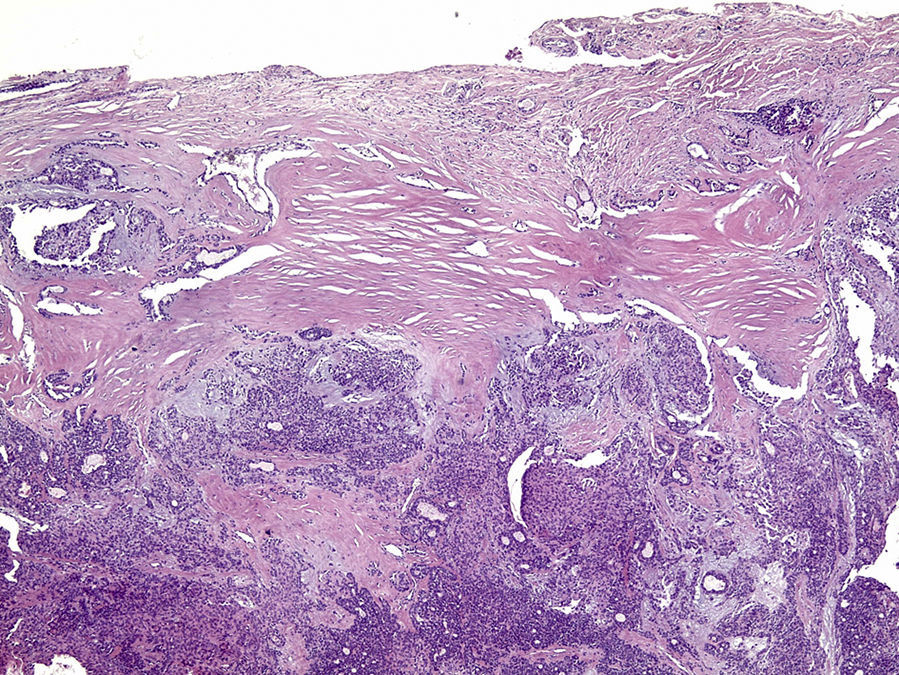

Os cortes histológicos, corados em hematoxilina e eosina, mostraram neoplasia de glândula salivar benigna, constituída por células epiteliais e mioepiteliais, parcialmente envolvida por fina cápsula de tecido conjuntivo fibroso (fig. 5). As células epiteliais encontravam‐se formando lençóis ou estruturas ductiformes, enquanto as células mioepiteliais formavam áreas mixoides, hialinas (fig. 6) ou exibiam aspecto plasmocitoide (fig. 7). O diagnóstico de adenoma pleomórfico foi confirmado. Paciente queixou‐se de desconforto no palato quando se alimentava, durante as 2 primeiras semanas após cirurgia. O paciente está sendo acompanhado clinicamente e, 2 anos após a cirurgia, não apresenta sinais de recidiva da lesão (fig. 8).

Os cortes histológicos mostraram neoplasia benigna de glândula salivar, envolvida por cápsula de tecido conjuntivo fibroso (fig. 14). O parênquima neoplásico é constituído por células epiteliais dispostas em lençóis e estruturas ductiformes, além de células mioepiteliais formando áreas mixoides e hialinas (fig. 15) ou apresentando‐se com morfologia plasmocitoide (fig. 16). O diagnóstico de adenoma pleomórfico foi confirmado. A paciente relatou ausência de dor no pós‐operatório e manteve utilização da placa de acrílico por 4 semanas. A paciente encontra‐se em acompanhamento e o exame clínico após 2 anos da remoção cirúrgica mostrou adequada cicatrização e ausência de sinais de recidiva da lesão (fig. 17).